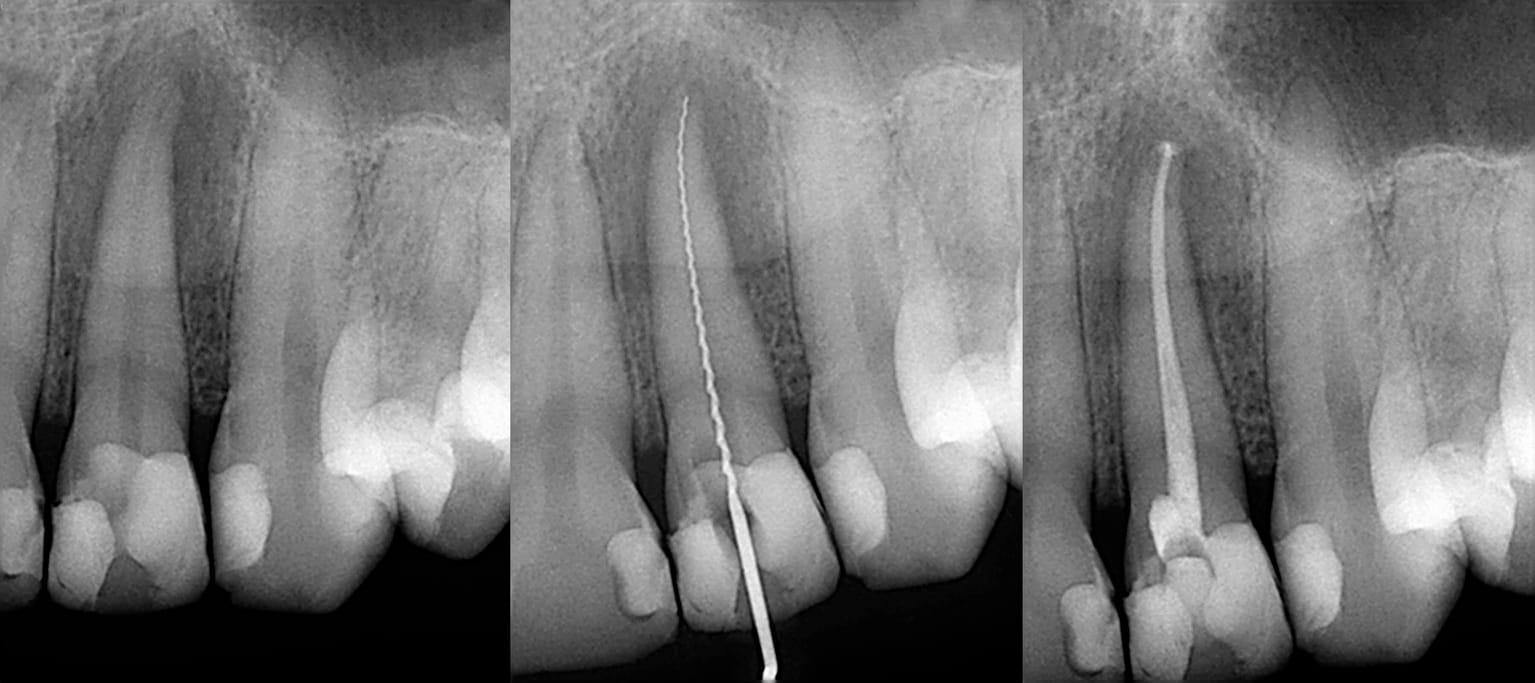

At Holmes Dental Care, we carry out root canal treatment in-house, using a state-of-the-art dental microscope and high-powered magnification for the most accurate results. Firstly, we take an x-ray to accurately check the root canals of your tooth and make sure there are no signs of infection in the surrounding bone. We plan your treatment, letting you know of each stage.

We use local anaesthetic to numb your tooth and minimise your discomfort during treatment. We place a rubber sheet around your tooth to keep it dry and to help you swallow comfortably during treatment. We carefully remove the infected pulp and flush the root canals with an antibacterial solution to thoroughly clean them.

We use special tiny instruments to shape the root canals before washing them again to remove any lasting debris. We then fill them with a flexible filling material called gutta-percha to seal the tooth and prevent any bacteria from entering and causing further infection.

The treated root canal is sealed with a permanent filling. In some cases, we may need to use a crown to help restore tooth shape and functionality for a natural looking finish.